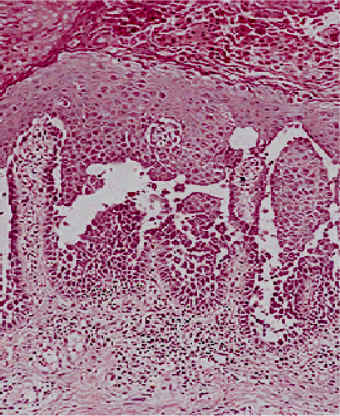

Acantosis: Aumento del grosor de la epidermis. también se observa hiperqueratosis, aumento del grosor de la capa córnea.

| Hiperqueratosis (aumento del grosor

de la capa córnea), Paraqueratosis (persitencia de los núcleos

de los queratinocitos en la capa córnea) y Acantosis (aumento

del grosor de la capa espinosa).